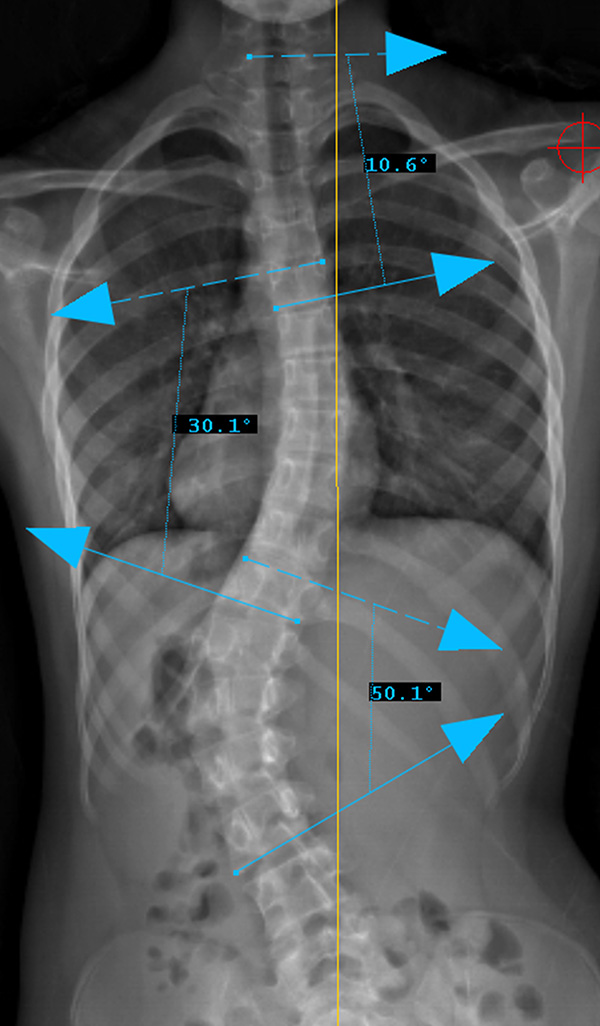

السر لنجاح حزام اعوجاج العمود الفقري حتى% 90 :تحسن زاوية كوب وانحراف الفقرة القمية عند تشخيص المراهق باعوجاج العمود الفقري مجهول السبب، يبدأ الأهل بطرح سؤال مهم: هل سينجح العلاج بحزام اعوجاج العمود الفقري